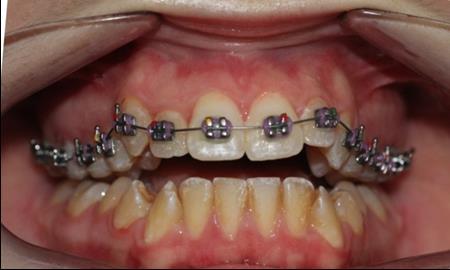

Figure 4.Intraoral photography at the start of the treatment.

After obtaining the informed consent the orthodontic treatment began and 0,22 Roth straight-wire fixed appliances were bonded. After leveling and aligning, during upper arch expansion, we took impressions and made intermediate study models. We noticed that palatal cusps of the upper premolars could not be intruded by classic mechanics. We decided to intrude first and second bicuspids to resolve the open bite. Skeletal anchorage was indicated and two orthodontic mini-implants were inserted on the palatal side between the premolars.